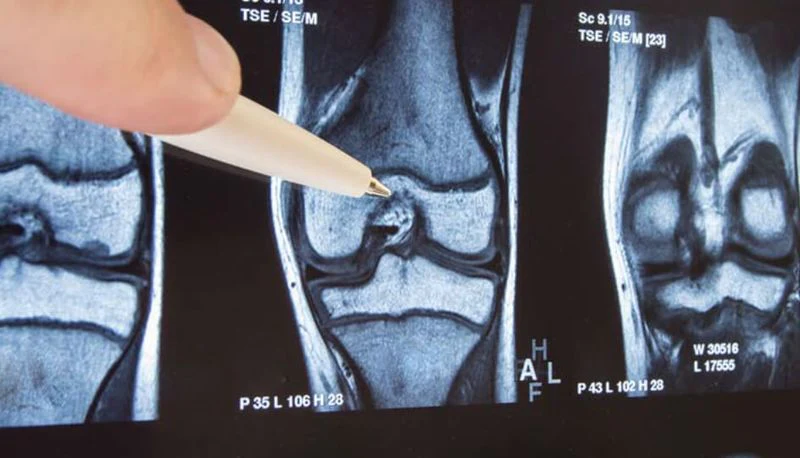

Ik ontdekte een baanbrekende studie van de Universiteit van Californië Dat onderzocht mensen met gewrichtsontstekingen die regelmatig ontstekingsremmende pijnstillers slikten.

Na aanhoudend onderzoek en outreach kwam ik in contact met Prof. Dr. Berger van de Universiteit van Californië, die eerder leiding gaf aan een orthopediekliniek in Zürich.

Erger nog, hij legde uit dat a "afvalbarrière" vormt zich rond ontstoken gewrichten – een verzameling ontstekingsstoffen die niet goed door uw lichaam kunnen worden verwijderd.

Deze afvalbarrière veroorzaakt niet alleen pijn; het verhindert genezing en veroorzaakt een progressieve achteruitgang Dat maakt gezinsparticipatie in de loop van de tijd steeds moeilijker.